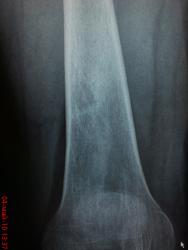

Здравствйте , коллеги! женщина, лет 40 , жалобы на хруст в левом коленном сустае при ходьбе. для сравнения сделали правый - и вот какая находка в дистальной трети правой бедренной кости (болит левый коленный сустав). Никаких жалоб на левую ногу нет. единственное , что помнит- была какая-то операция , со слов на м.тканях, как раз в этой области лет 10 назад - "был гной". связанно ли это с находкой или нет не знаю. Вижу 2 очага со склеротичесим ободком без клиники, надкостница и м.ткани вроде не реагируют. как вы думаете , что это может быть?

Скорее всего это ассимилированные периостальные наслоения, остеосклероз. Если так, то вероятен залеченный остеомиелит.

Очень смутила минералопения в метафизе, причем выраженная... и деструкция...

Жалоб никаких. признаки остеопении быть может из-за обработки снимков(подыграл светом и тенью). на р-граммах коленных суставов в 2-х пр-ях - структура костей , кроме этих очагов разряжения , вполне нормальная...

все доброкачественное из образований - эпиметафиз, для злого - нужна клиника , отсутствие склероза. может Фиброзный кортикальный дефект?

Это ни краевой кортикальный дефект для которого характерно наличие кортикального склероза с фестончатыми краями, ограниченного замыкательной пластинкой. В данном случае имеется разряжение костной ткани ближе к овоидной форме, края четко визуализируются уплотнены, это кистовидное просветление, надо отметить режим без особенности,  даже мягкие ткани визуализируются, что при жестком снимке не было бы, а значит и остеопороз явно на лицо, да и с учетом возраста, признаки умеренного остеопороза есть. Если смущает наличие кисты, можите провести рентген-контроль через 6 месяцев, ни чего злокачественного нет и это самое главное.

Киста и не чего большего, на фоне чего остается только догадываться, а замыкательная пластинка это "кортикал".

Написал бы Последствия перенесённого остиомиелита. Костная киста. Рентген контроль через  6 мес.

А я вижу очаг фиброзной дисплазии. А утолщение кортикального слоя - возможно, просто утолщение кортикального слоя после перенесенного заболевания мягких тканей.